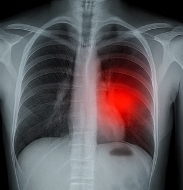

폐결절이란 상태의 진단 방법

폐결절이란 상태를 확인하기 위해 병원에서는 다양한 진단 검사를 시행합니다.

- 흉부 X-ray: 기본 검사.

- 저선량 흉부 CT: 작은 결절도 확인 가능.

- PET-CT: 악성 여부 평가.

- 조직검사: 확정 진단.

폐결절이란 상태는 영상검사와 조직검사를 통해 최종적으로 진단됩니다.